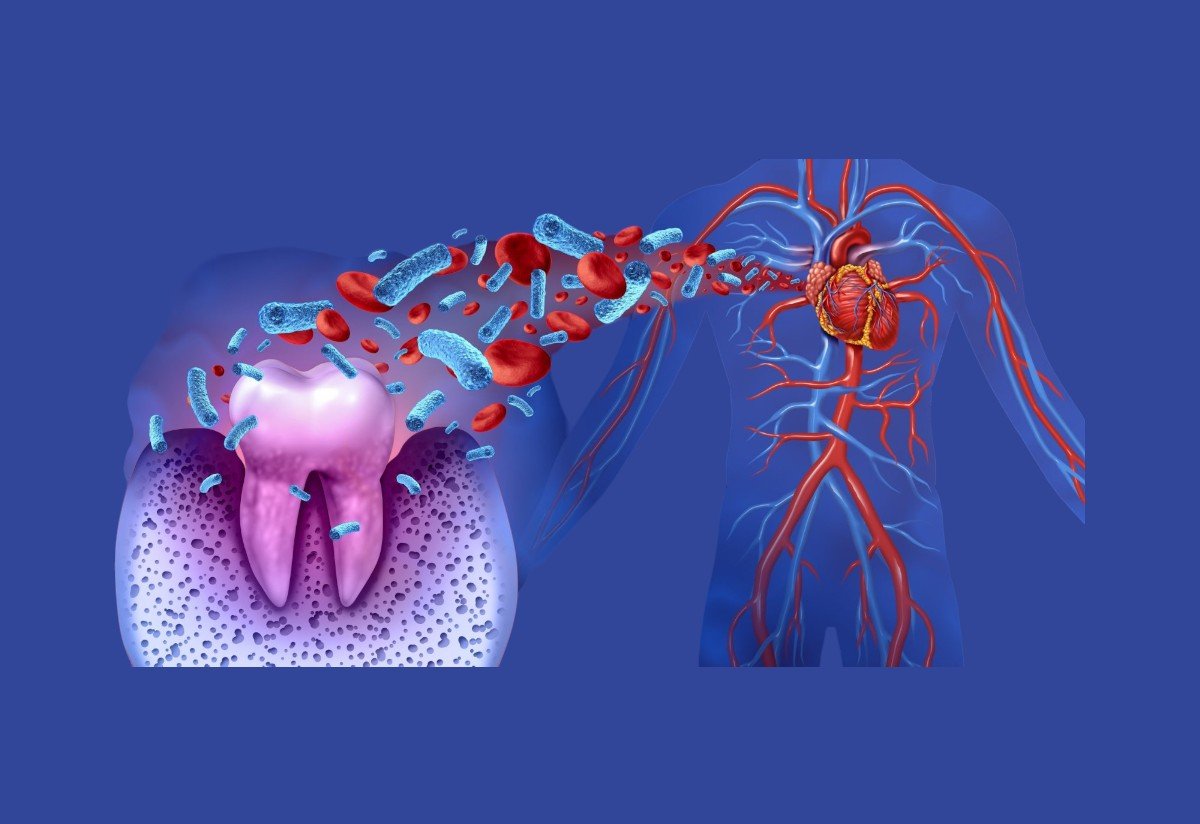

Diş İmplantları: Titanyum implantlar eksik dişlerin yerini alır ve porselen veya zirkonyum kronlarla doğal bir görünüm sağlar...

ASDENT Ağız ve Diş Sağlığı Kliniği’nde eksik dişler için kalıcı, estetik ve fonksiyonel çözümler sunuyoruz. İmplant tedavisi sayesinde hem çiğneme fonksiyonlarınızı hem de estetik görünümünüzü yeniden kazanabilirsiniz. Modern teknoloji, deneyimli hekim kadromuz ve yüksek kaliteli implant markaları ile tedavilerimiz uzun ömürlü ve güvenlidir.